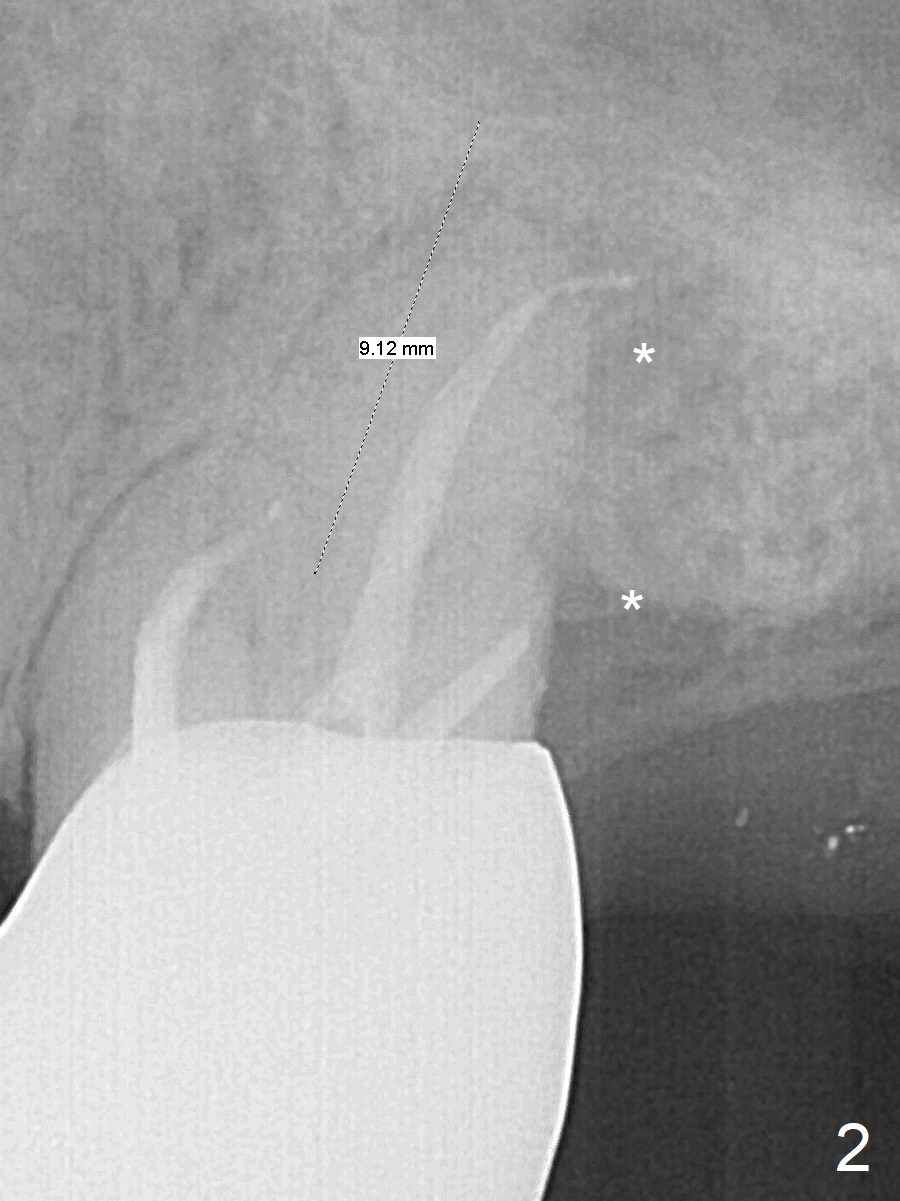

A 53-year-old man cannot chew on the left side with distal abscess in spite of RCT for #14 (* in Fig.1,2 (taken 11 ad 21 months postop, respectively)). After extraction (Fig.3 (CBCT coronal section) black area), start osteotomy with 2 mm drill (red outline) in the septum buccal to the palatal (P) socket). Following 2 mm drill removal (Fig.4), use 4.3 mm Magic Drill (red outline) for ~ 9 mm. When the osteotomy is being done, the osteotomy most likely shifts palatal (Fig.5 arrow) because of thin bone palatally. When the MD is removed (Fig.6), use Magic Sinus Lifter (Fig.7 pink) for sinus lift (arrow). The implant is to be 5x11 mm or larger. Because of the distal defect (Fig.1,2), start osteotomy mesially. Take Alginate impression before surgery for possible orthodontic treatment. Since bone density is high, use higher voltage and longer time for X-ray.